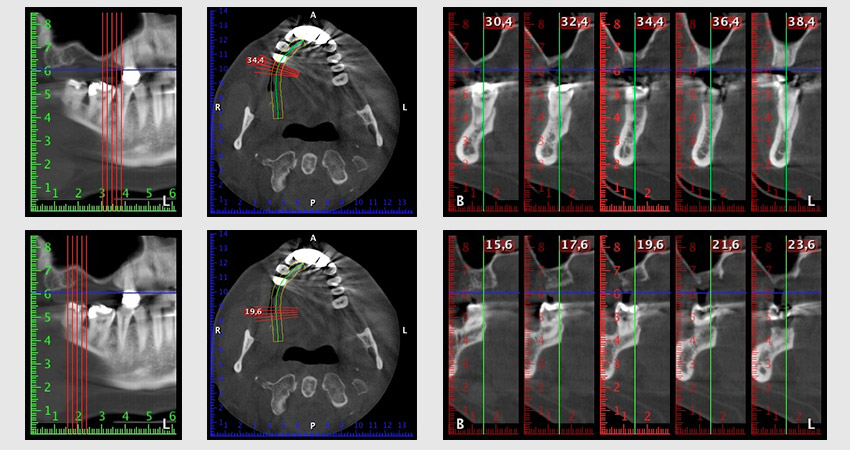

Шест месеца след екстракцията на зъби 16 и 14 се извършва преглед с дигитален томограф (DVT, Planmeca), с цел планиране и намаляване на възможните рискове. Ясно се вижда, че костта не се е регенерирала до желания обем (Фиг. 2 до 7).